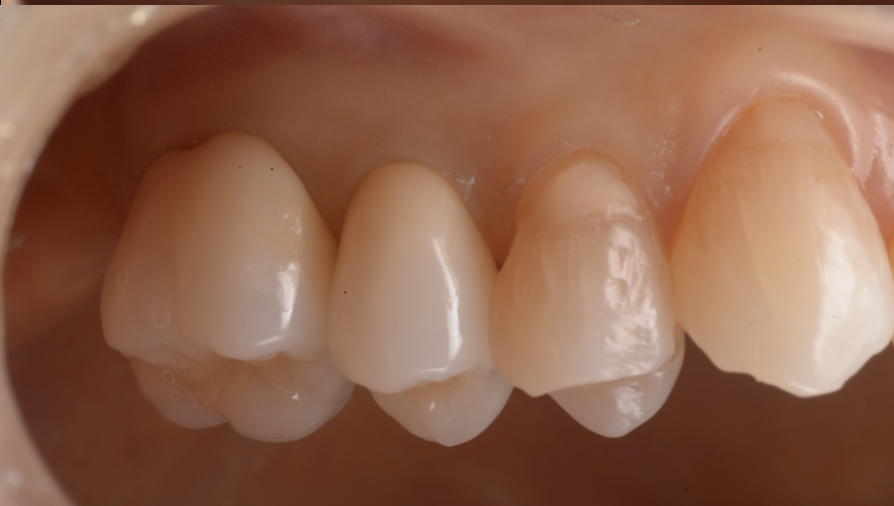

治療前後比較

治療後

セラミック素材を活用することで、透明感のある自然な色合いを再現できます。

周囲の歯に合わせた色調を調整し、「被せ物だと気づかれない」自然な笑顔を目指します。